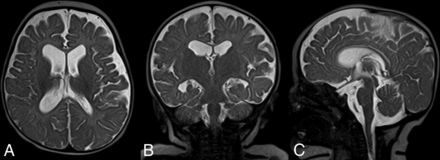

UFB-MRI demonstrates fluid-containing structures well against the brain parenchyma and calvaria. We hypothesized that UFB-MRI can be used beyond shunted hydrocephalus for indications such ventriculomegaly (Figs 1⇓–3), macrocephaly (Fig 4), or intracranial cyst (Fig 5) without adverse outcomes.

UFB-MRI performed in axial (A), sagittal (B), and coronal (C) planes with HASTE in a 1-day-old male infant with natural sleep. The study indication was a prenatal diagnosis of ventriculomegaly. Note the mild enlargement of the supratentorial ventricles and normal size of the fourth ventricle. There were no clinical signs of increased intracranial pressure. Although the cerebral aqueduct patency evaluation was limited in this study, the patient was followed with UFB-MRI. No additional standard MRI was deemed clinically necessary (Fig 2).